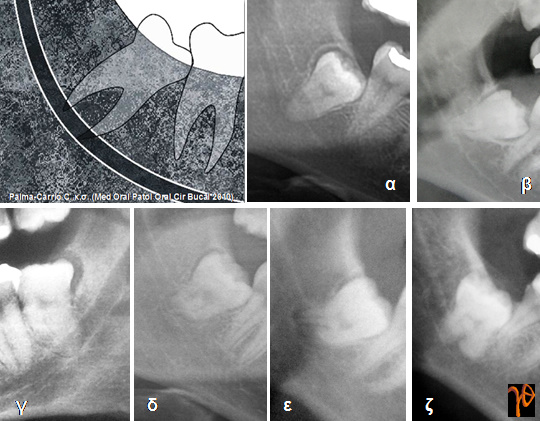

Στις εικόνες που ακολουθούν υπενθυμίζονται κάποιες από αυτές τις περιπτώσεις στις οποίες θα πρέπει να δίνεται ιδιαίτερη προεγχειρητική και χειρουργική προσοχή:

Εικόνα 3. Ακτινοδιαπερατές περιοχές ελαττωμένης πυκνότητας των ριζών [Σχέδιο και Ακτινογραφίες (α-ζ)]

Εικόνα 4. Απόκλιση του γναθιαίου πόρου [Σχέδιο και Ακτινογραφίες (α,β)]